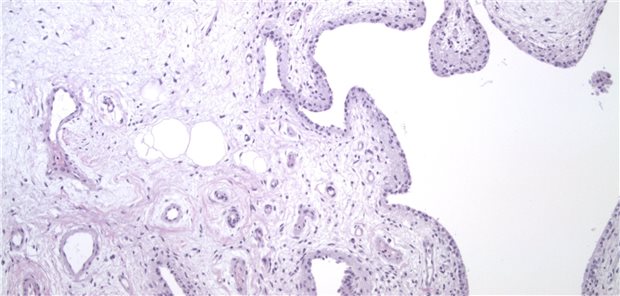

Kolorektale Polypen bis zu einer Größe von 20 mm werden koloskopisch häufig nicht vollständig reseziert, wie Forscher in einer Übersichtsanalyse festgestellt haben.